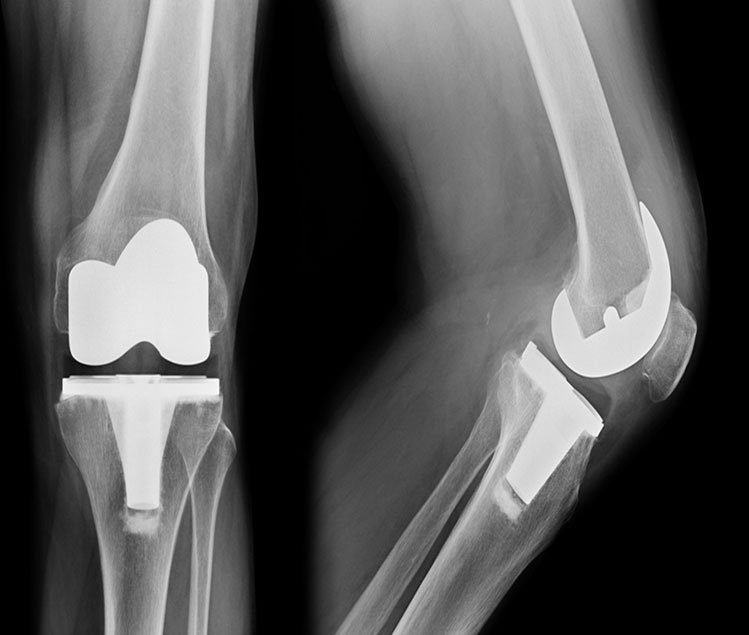

Total Knee Joint Replacement (TKR) revision surgery is an orthopaedic surgical procedure in which the prosthetic pieces(s) of the previous TKR surgery are removed. New prosthetic pieces are then replaced within the knee joint. The components consist of the femoral condyle component, the tibial plateau component, the polyethylene spacer and the patella component. All or some of these may be replaced depending on the reason for replacement.

Revisional TKR surgery is a more complicated operation requiring longer time in theater and rehabilitation is slower and takes a more cautious approach.